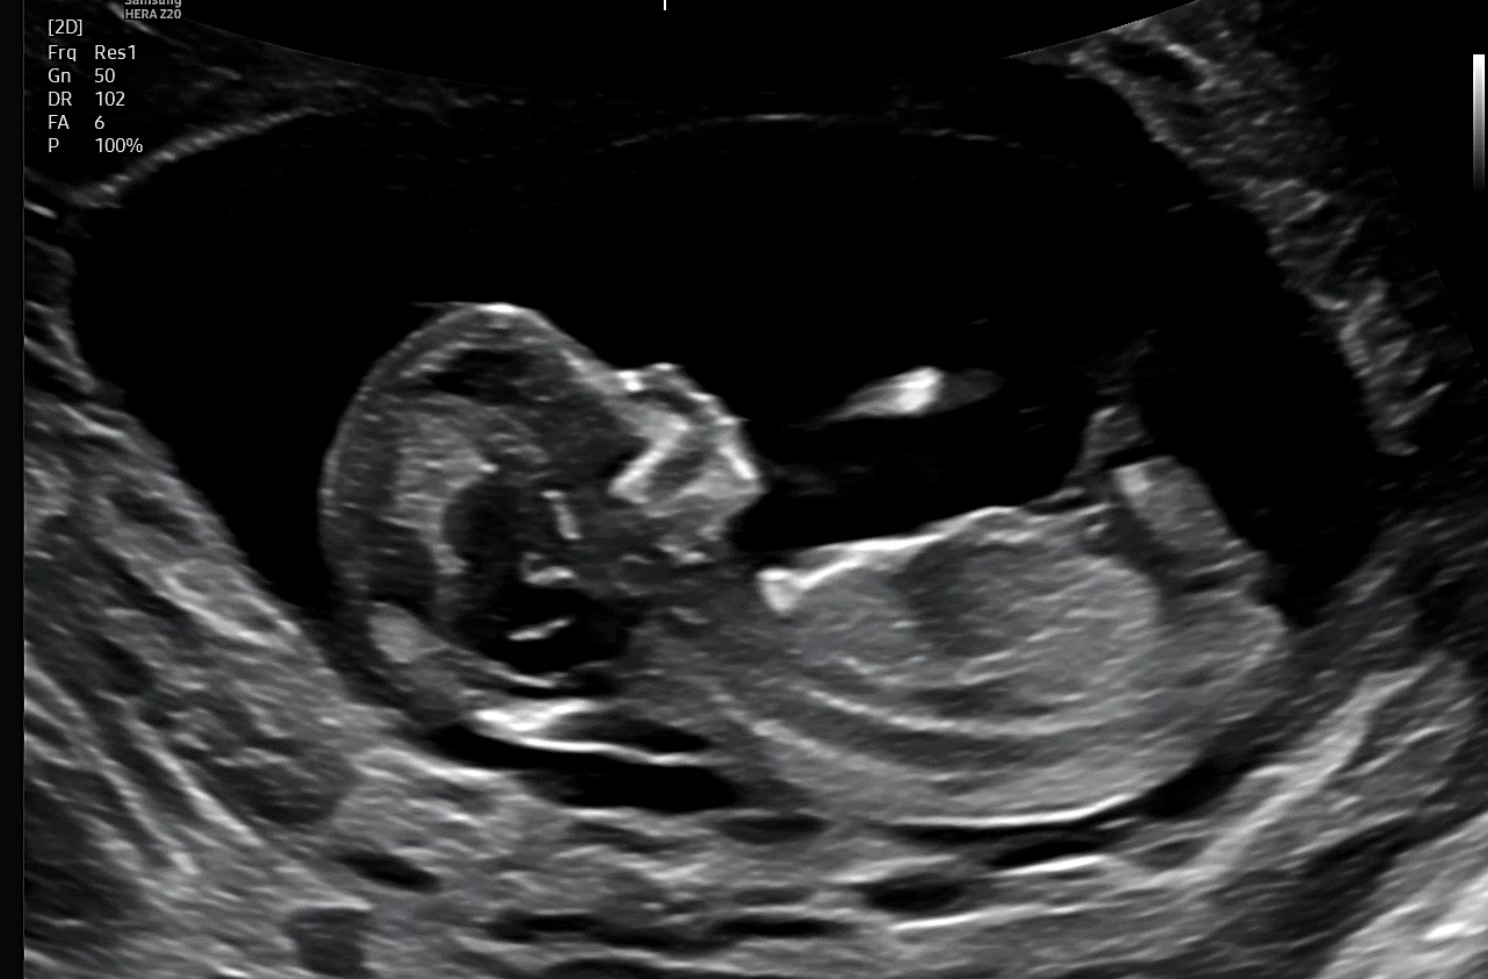

[12주 4일차] 성별 각도법 투표부탁드려요 :)

남편은 딸이라고 하는데 저는 도저히 모르겠어서요! 성별 투표 부탁드려요 👼🏻💛💛 +추가 베이비빌리 각도법 링크에서 테스트해보니 딸 70%라네요🙈 니프티했는데 성별 얼른 알고 싶네용💛💛💛 ++추가 니프티 검사 Y염색체 미검출로 딸 입니다!!!! 투표해주셔서 감사했습니당 👼🏻